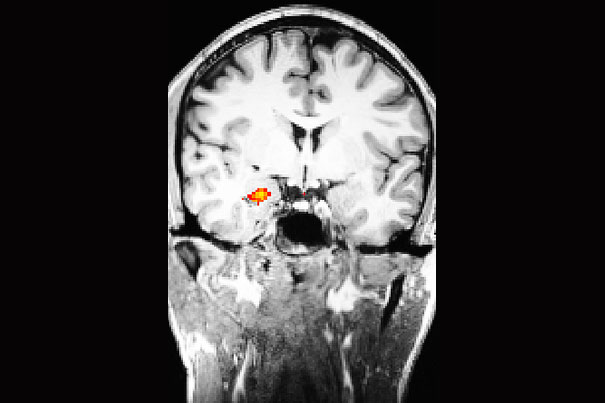

Erasing traumatic memories

Researchers at Harvard-affiliated McLean Hospital are reporting that xenon gas, used in humans for anesthesia and diagnostic imaging, has the potential to be a treatment for post-traumatic stress disorder (PTSD) and other memory-related disorders